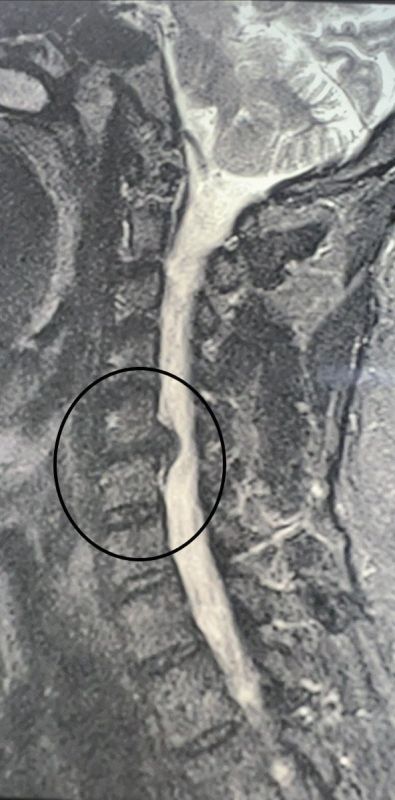

В конце октября в больницу обратился 49-летний мужчина, у которого месяц болела шея. Кроме того, пациент жаловался на онемение и слабость в правой руке. Ранее мужчина проходил лечение, но оно не помогло. Врачи обнаружили грыжу...